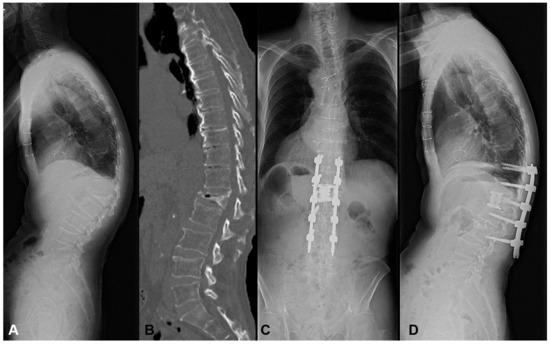

3.1.2. Case 2: 77 Years Old, Male, L1 Vertebral Collapse

He suffered from a progressive L1 vertebral collapse after a compression fracture by falling down. Due to intractable pain, he was unable to walk without a support preoperatively. The MIS L1 corpectomy, artificial body replacement, and L2/3 OLIF were performed followed by single-position percutaneous screw fixation (Figure 5). Even the LK of 42 degrees and PI-LL of 16 degrees were corrected to 19 degrees and 8 degrees, respectively. However, the distal screw pulled out at 1 month postoperatively. The patient required hardware removal after the complete fusion at 1 year postoperatively.

Figure 5.

A 77-year-old male suffering from L1 vertebral collapse. The MIS L1 corpectomy, artificial body replacement, and L2/3 OLIF were performed followed by single-position percutaneous screw fixation. However, the distal screw pulled out at 1 month postoperatively. (A) Preoperative lateral X-ray, (B) Preoperative CT, (C) Standing AP X-ray at one month postoperatively, (D) Standing lateral X-ray at one month postoperatively.

In this case, we conducted additional enhancement of L2/3 OLIF to prevent MC. However, the local kyphosis was not corrected efficiently (19 degrees). This exceeded our obtained threshold of 11 degrees, leading to DJK in this case.